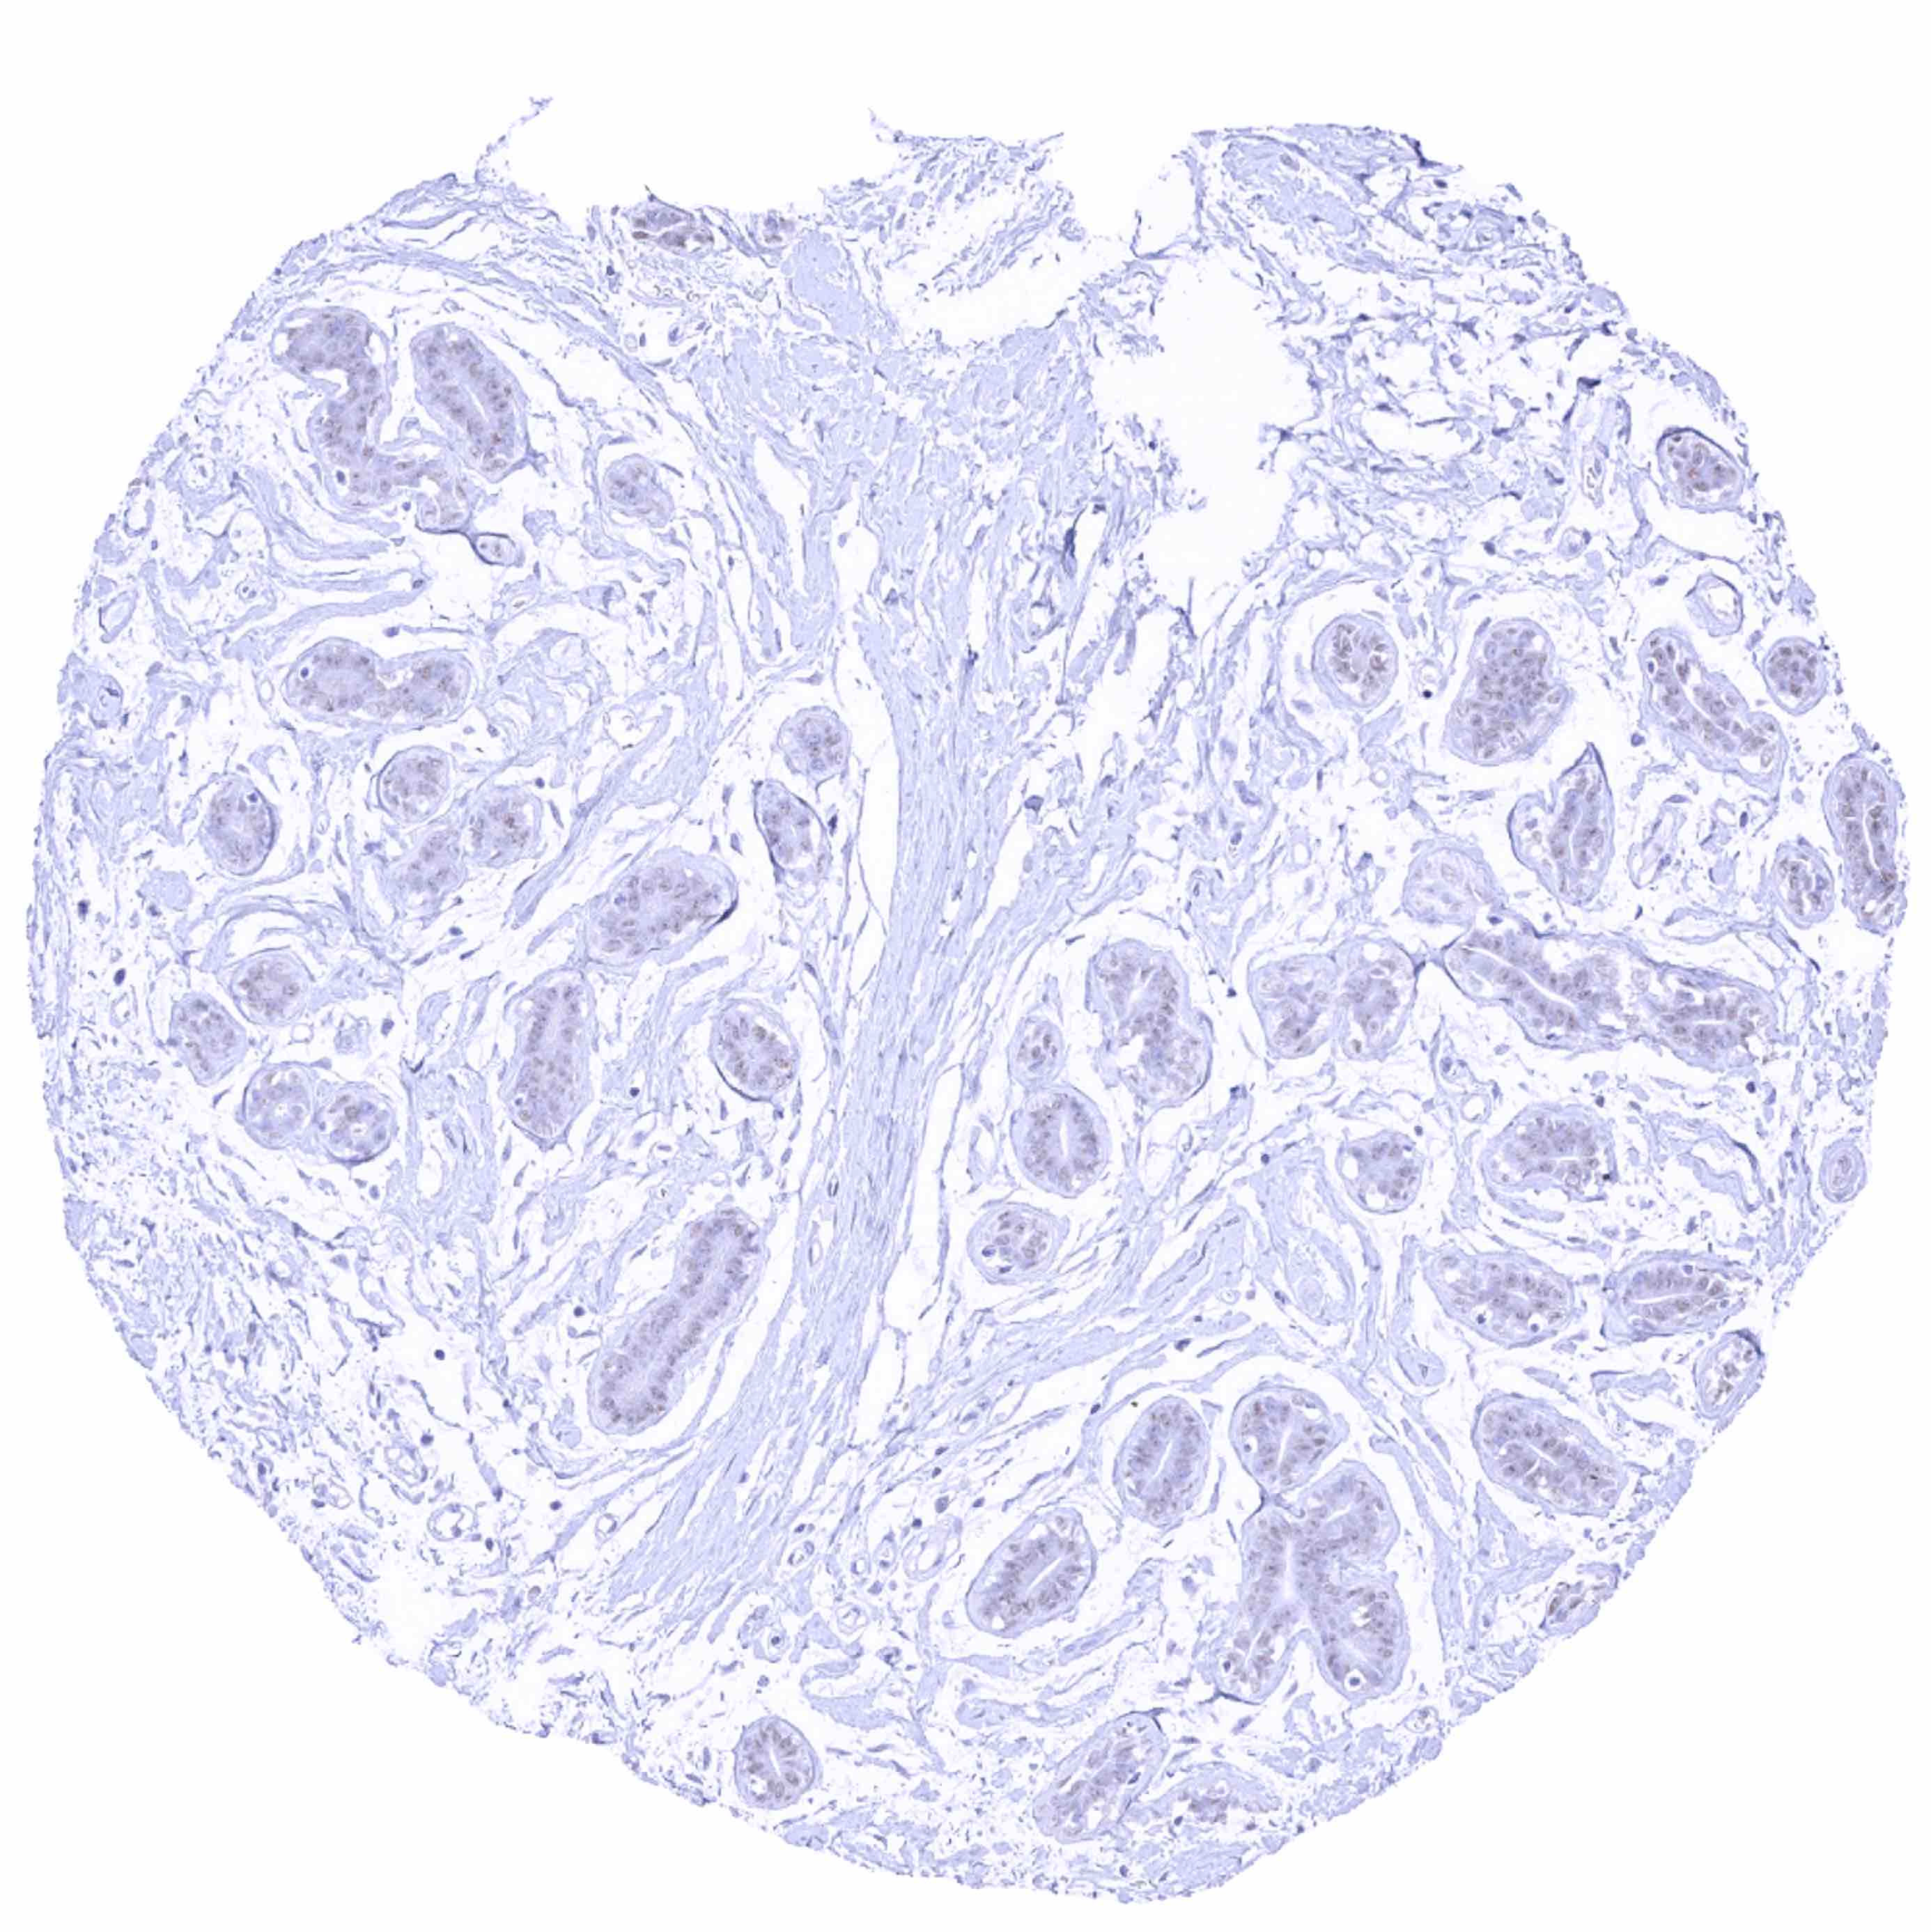

Prostate – Strong SOX2 positivity of a fraction of basal cells